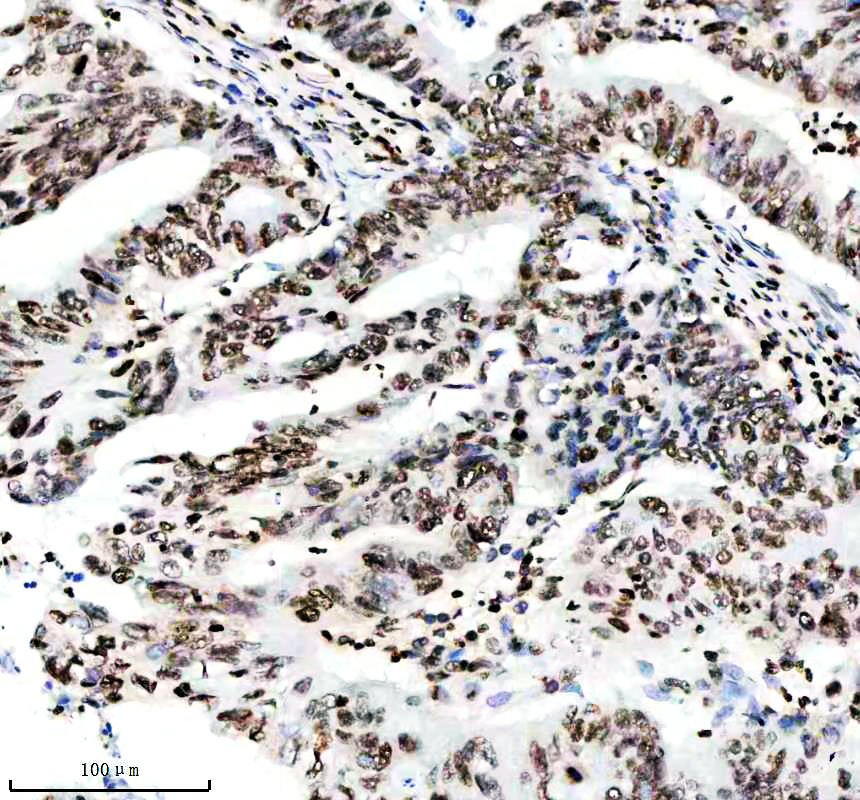

IHC analysis of Histone H3 (acetyl K14) using anti-Histone H3 (acetyl K14) antibody (BM4151) .

Histone H3 (acetyl K14) was detected in a paraffin-embedded section of human rectal cancer tissue. The tissue section was incubated with rabbit anti-Histone H3 (acetyl K14) Antibody (BM4151) at a dilution of 1:200 and developed using HRP Conjugated Rabbit IgG Super Vision Assay Kit (Catalog # SV0002) with DAB (Catalog # AR1027) as the chromogen.

IHC analysis of Histone H3 (acetyl K14) using anti-Histone H3 (acetyl K14) antibody (BM4151) .

Histone H3 (acetyl K14) was detected in a paraffin-embedded section of human rectal cancer tissue. The tissue section was incubated with rabbit anti-Histone H3 (acetyl K14) Antibody (BM4151) at a dilution of 1:200 and developed using HRP Conjugated Rabbit IgG Super Vision Assay Kit (Catalog # SV0002) with DAB (Catalog # AR1027) as the chromogen.